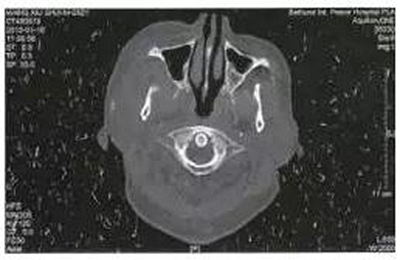

病例2,女,28歲。于1月前拔除右側(cè)上頜第三磨牙,3天后出現(xiàn)右側(cè)顳部劇烈疼痛,張口度15 mm,經(jīng)多家醫(yī)院保守治療效果不佳。CT掃描顯示右側(cè)咬肌及顳下間隙軟組織腫脹,右側(cè)髁突內(nèi)側(cè)有少量死骨形成(圖2)。入院后全麻下采用口內(nèi)入路手術(shù),刮除死骨,引流膿液,放置引流條。術(shù)后1月復查,張口度達到25 mm。

圖2右側(cè)髁突骨髓炎,死骨形成